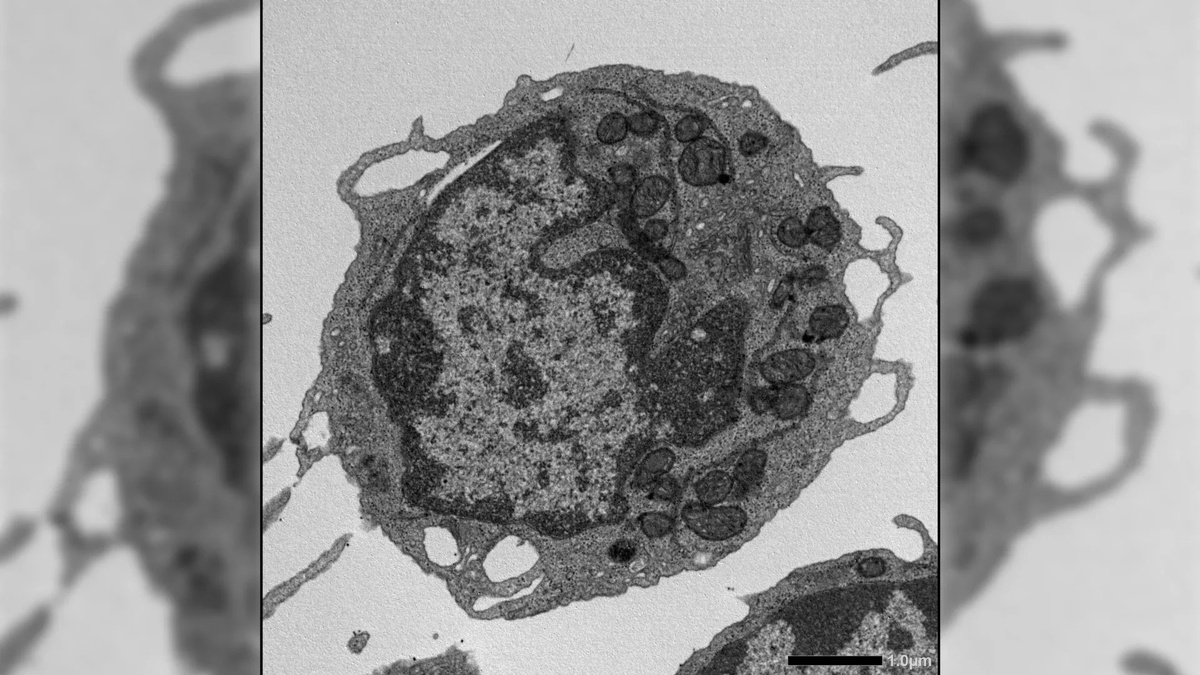

Наши стволовые клетки крови — это настоящие фабрики жизни, но со временем они постепенно теряют свою силу. Группа ученых из Японии и США обнаружила неожиданного виновника этого процесса. Оказалось, что белок MLKL, известный как триггер клеточной смерти, ведет скрытую двойную игру 🧬. Под воздействием возрастного стресса он не убивает клетки, а проникает в их энергетические станции — митохондрии — и буквально выводит их из строя. Это лишает кровь способности обновляться, а наш иммунитет — надежной защиты. Исследователи доказали: если заблокировать работу MLKL, стволовые клетки сохраняют молодость и продуктивность даже в глубокой старости. Это открытие открывает путь к созданию лекарств нового типа, которые помогут организму восстанавливаться после химиотерапии и защитят нас от старения 🩸. А вы бы хотели «перезагрузить» свои клетки, чтобы они всегда работали как в восемнадцать лет?